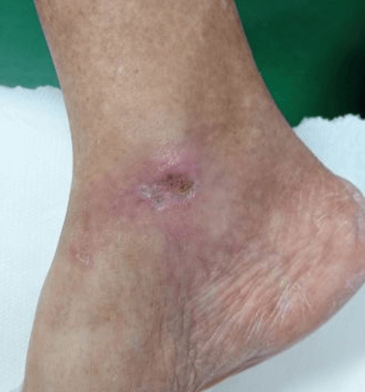

Advanced Wound Care

• Chronic diabetic ulcers

• Venous leg ulcers

Intact collagen dressings achieved complete wound closure in 78% of diabetic foot ulcer cases at 12 weeks — nearly double the rate observed with standard hydrolyzed collagen or standard-of-care dressings.